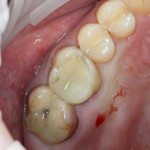

На приведенных фотографиях заметно, как изменились линейные размеры альвеолярного гребня с момента удаления 26 и установки импланта, до его интеграции (сравните толщину). Но это не так критично, и позволяет получить хороший результат протезирования:

Однако, если одной из задач имплантологического лечения является максимальное сохранение окружающих зуб тканей, то без использования биоматериалов вряд удастся обойтись. На фотографии ниже: вроде как, проведена немедленная имплантация, но последующая атрофия альвеолярного гребня вконец испортила эстетический результат лечения.

Не только фронтальная группа зубов требует внимания с точки зрения эстетики — некоторые пациенты хотят, чтобы и в боковом участке «зуб был неотличим от настоящего». И в этих случаях мы также используем биоматериалы, чтобы сохранить на месте костные стенки лунки и получить хороший эстетический и функциональный результат: